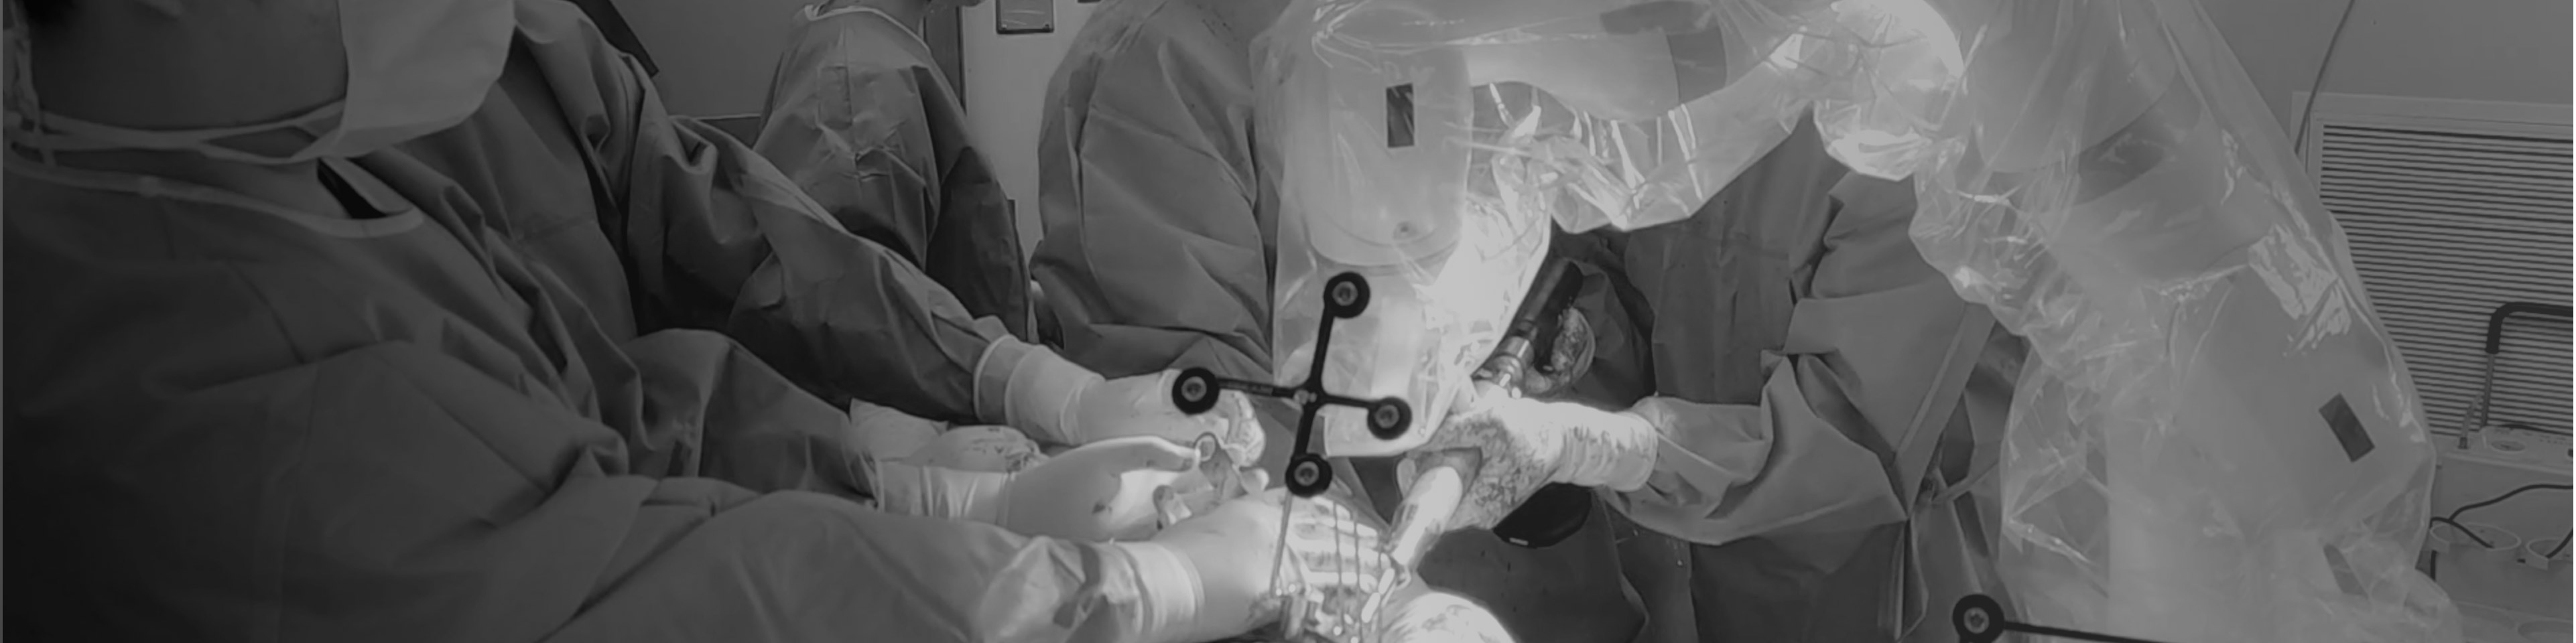

· 零重力操作與精準(zhǔn)力反饋,人機(jī)交互體驗(yàn)流暢。

· 多種運(yùn)動(dòng)模式,操作高效省力。

· 精準(zhǔn)執(zhí)行手術(shù)方案,消除徒手操作誤差。